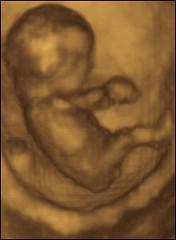

Promoting Female abortion

Is Ultrasound ads in Canadian Punjabi newspapers promoting female abortion?

Ultrasound